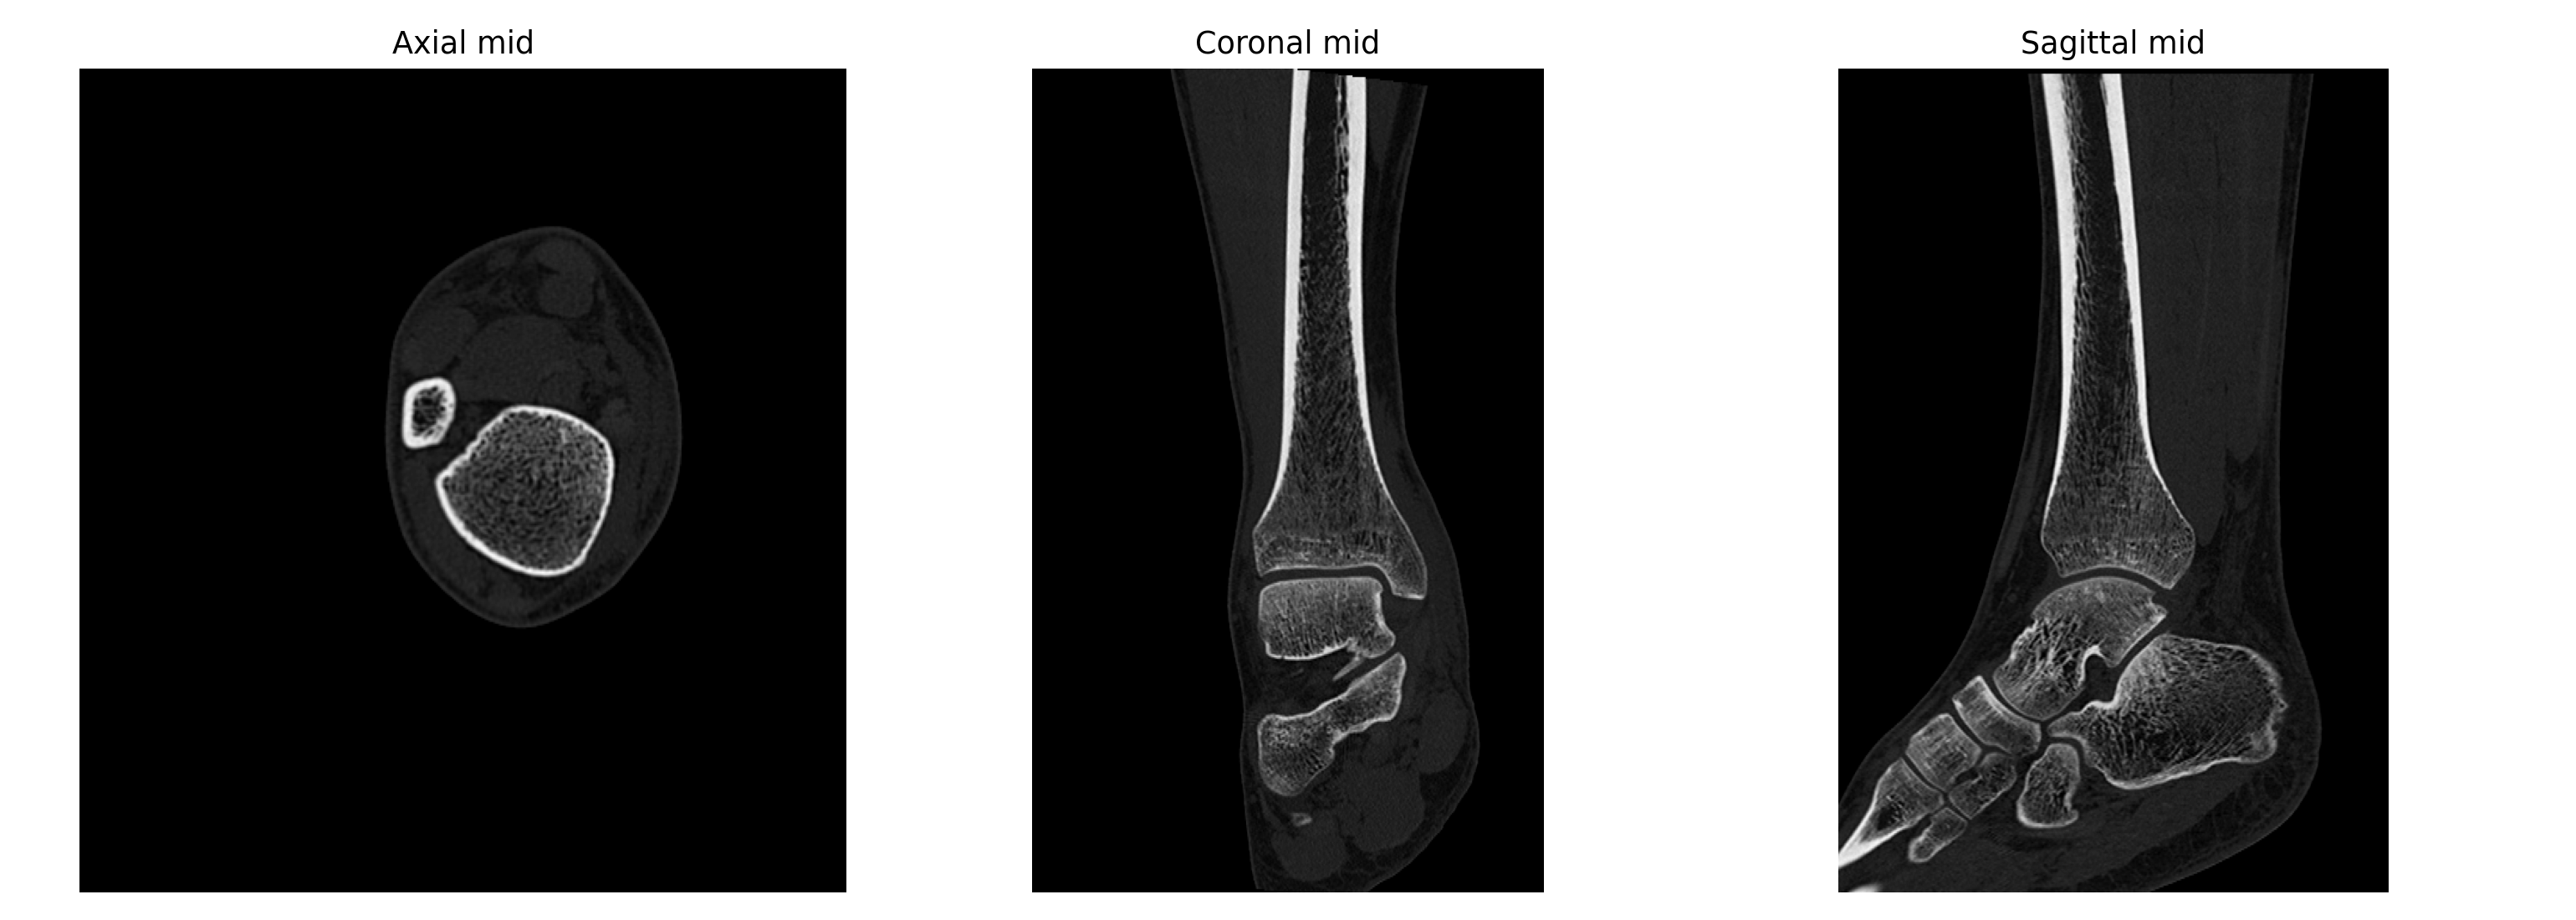

基于 2026-04-02 右踝无对比 CT 原始 DICOM 的辅助分析。核心问题是: 右踝外侧、距骨外侧突及距下关节外侧附近存在高概率关节内骨性损伤, 表现更接近单板滑雪常见的 snowboarder’s fracture。

- 冠状位、矢状位和三维辅助重建里都能反复看到局部骨性不规则和分离感。

三维与关键切面

三维图更适合看骨片和关节面的空间关系;真正判断骨折线、关节面台阶和位移, 仍然要以原始 CT 切面为主。